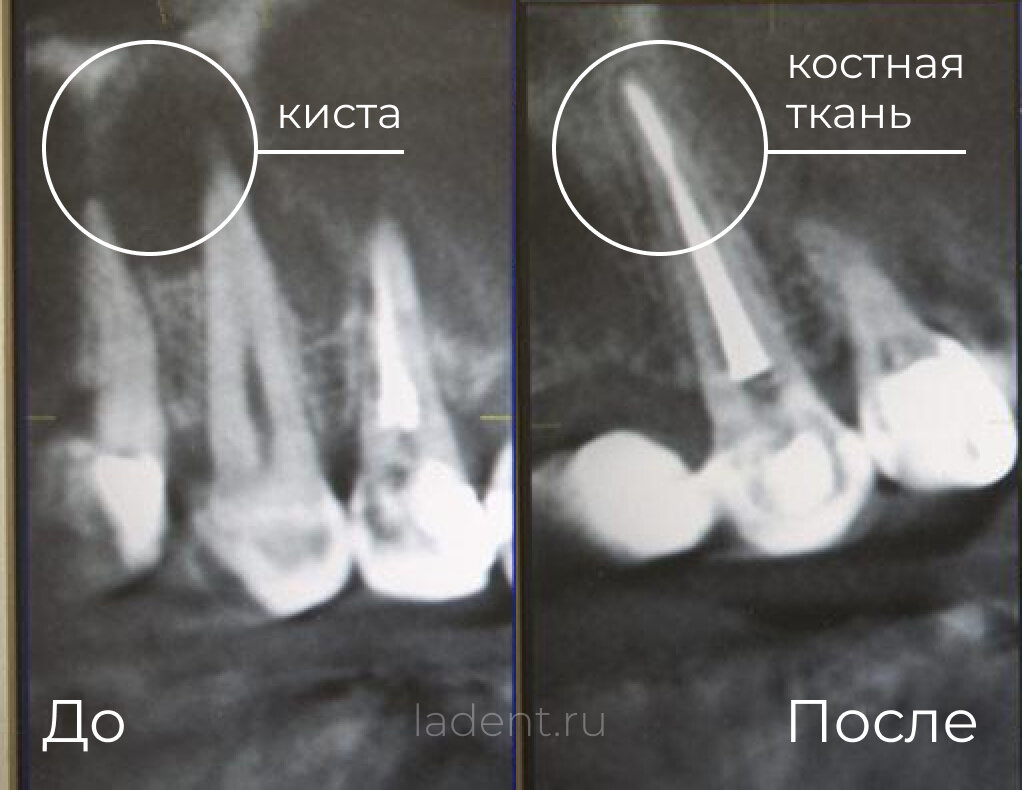

Киста — это полость в кости, заполненная жидкостью или другим содержимым. Она образуется вследствие воспалительного процесса или травмы зуба. Многие считают, что при обнаружении кисты зуб уже не спасти, но это не так.

Современная стоматология располагает методами, которые позволяют сохранить зуб даже при значительном размере кисты. Ключевую роль здесь играет использование операционного микроскопа. Благодаря многократному увеличению и яркому освещению врач может: